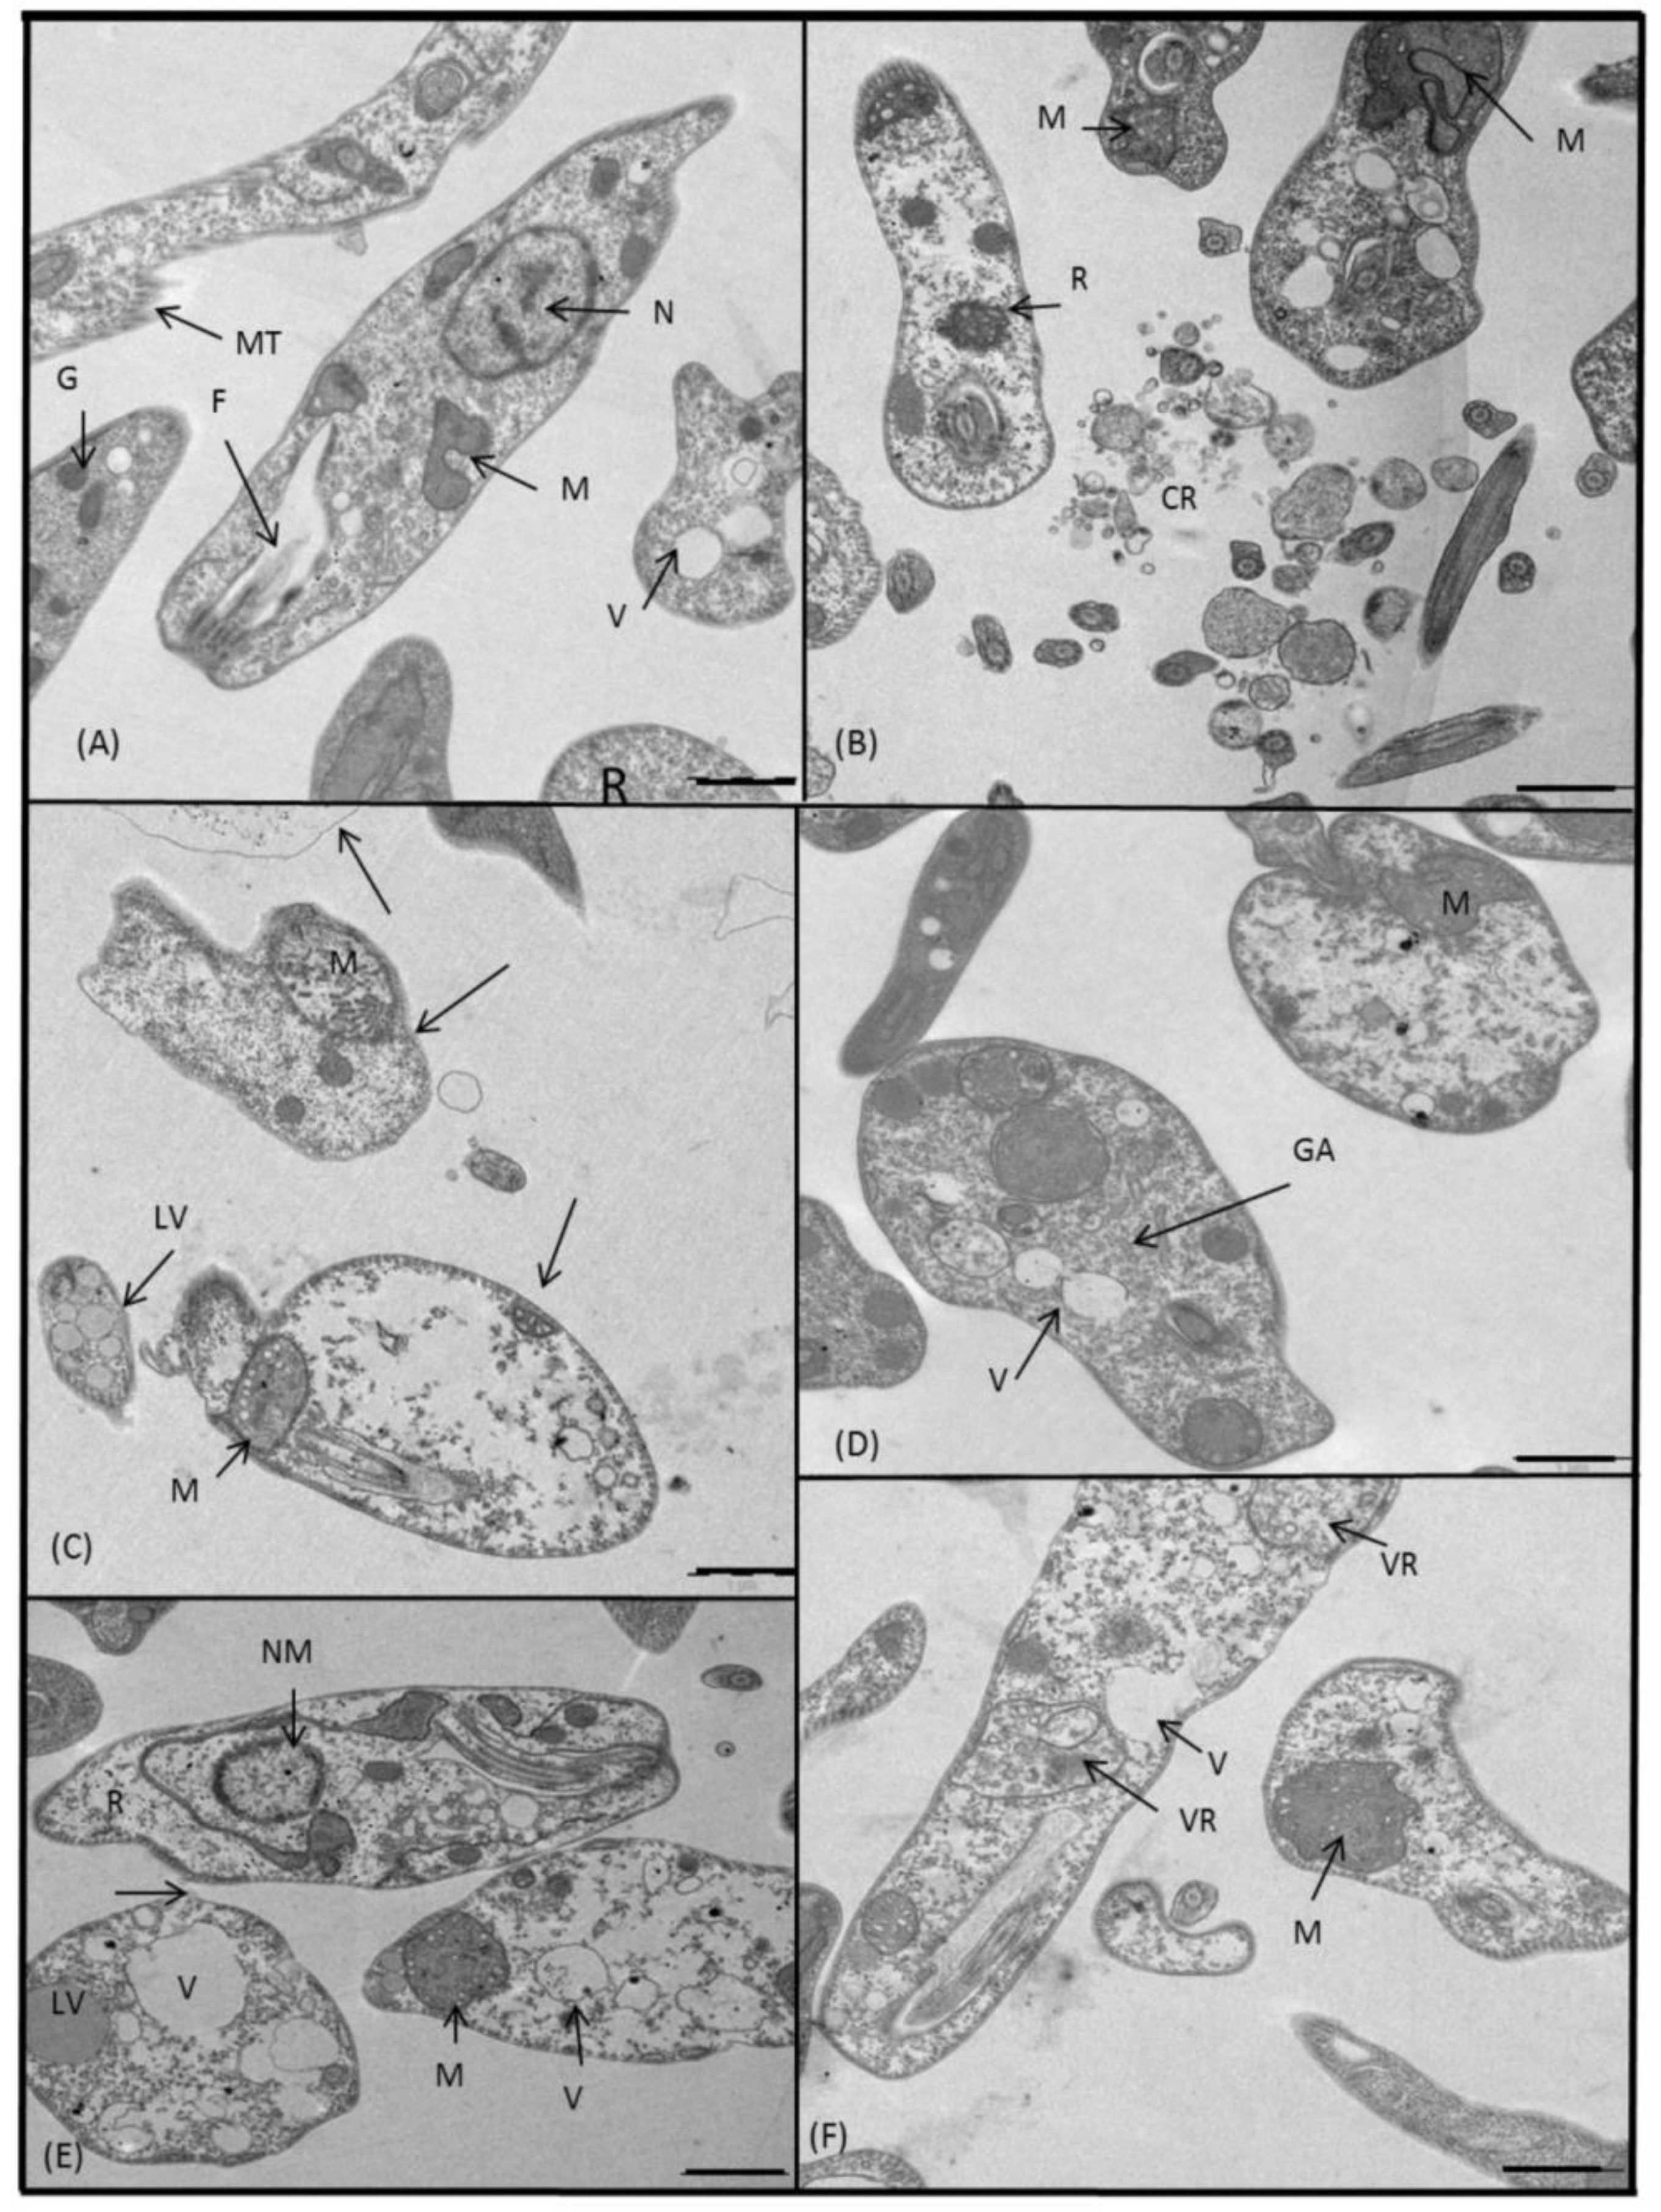

2.3.3. Microscopy

4.5. Ultrastructural Alterations